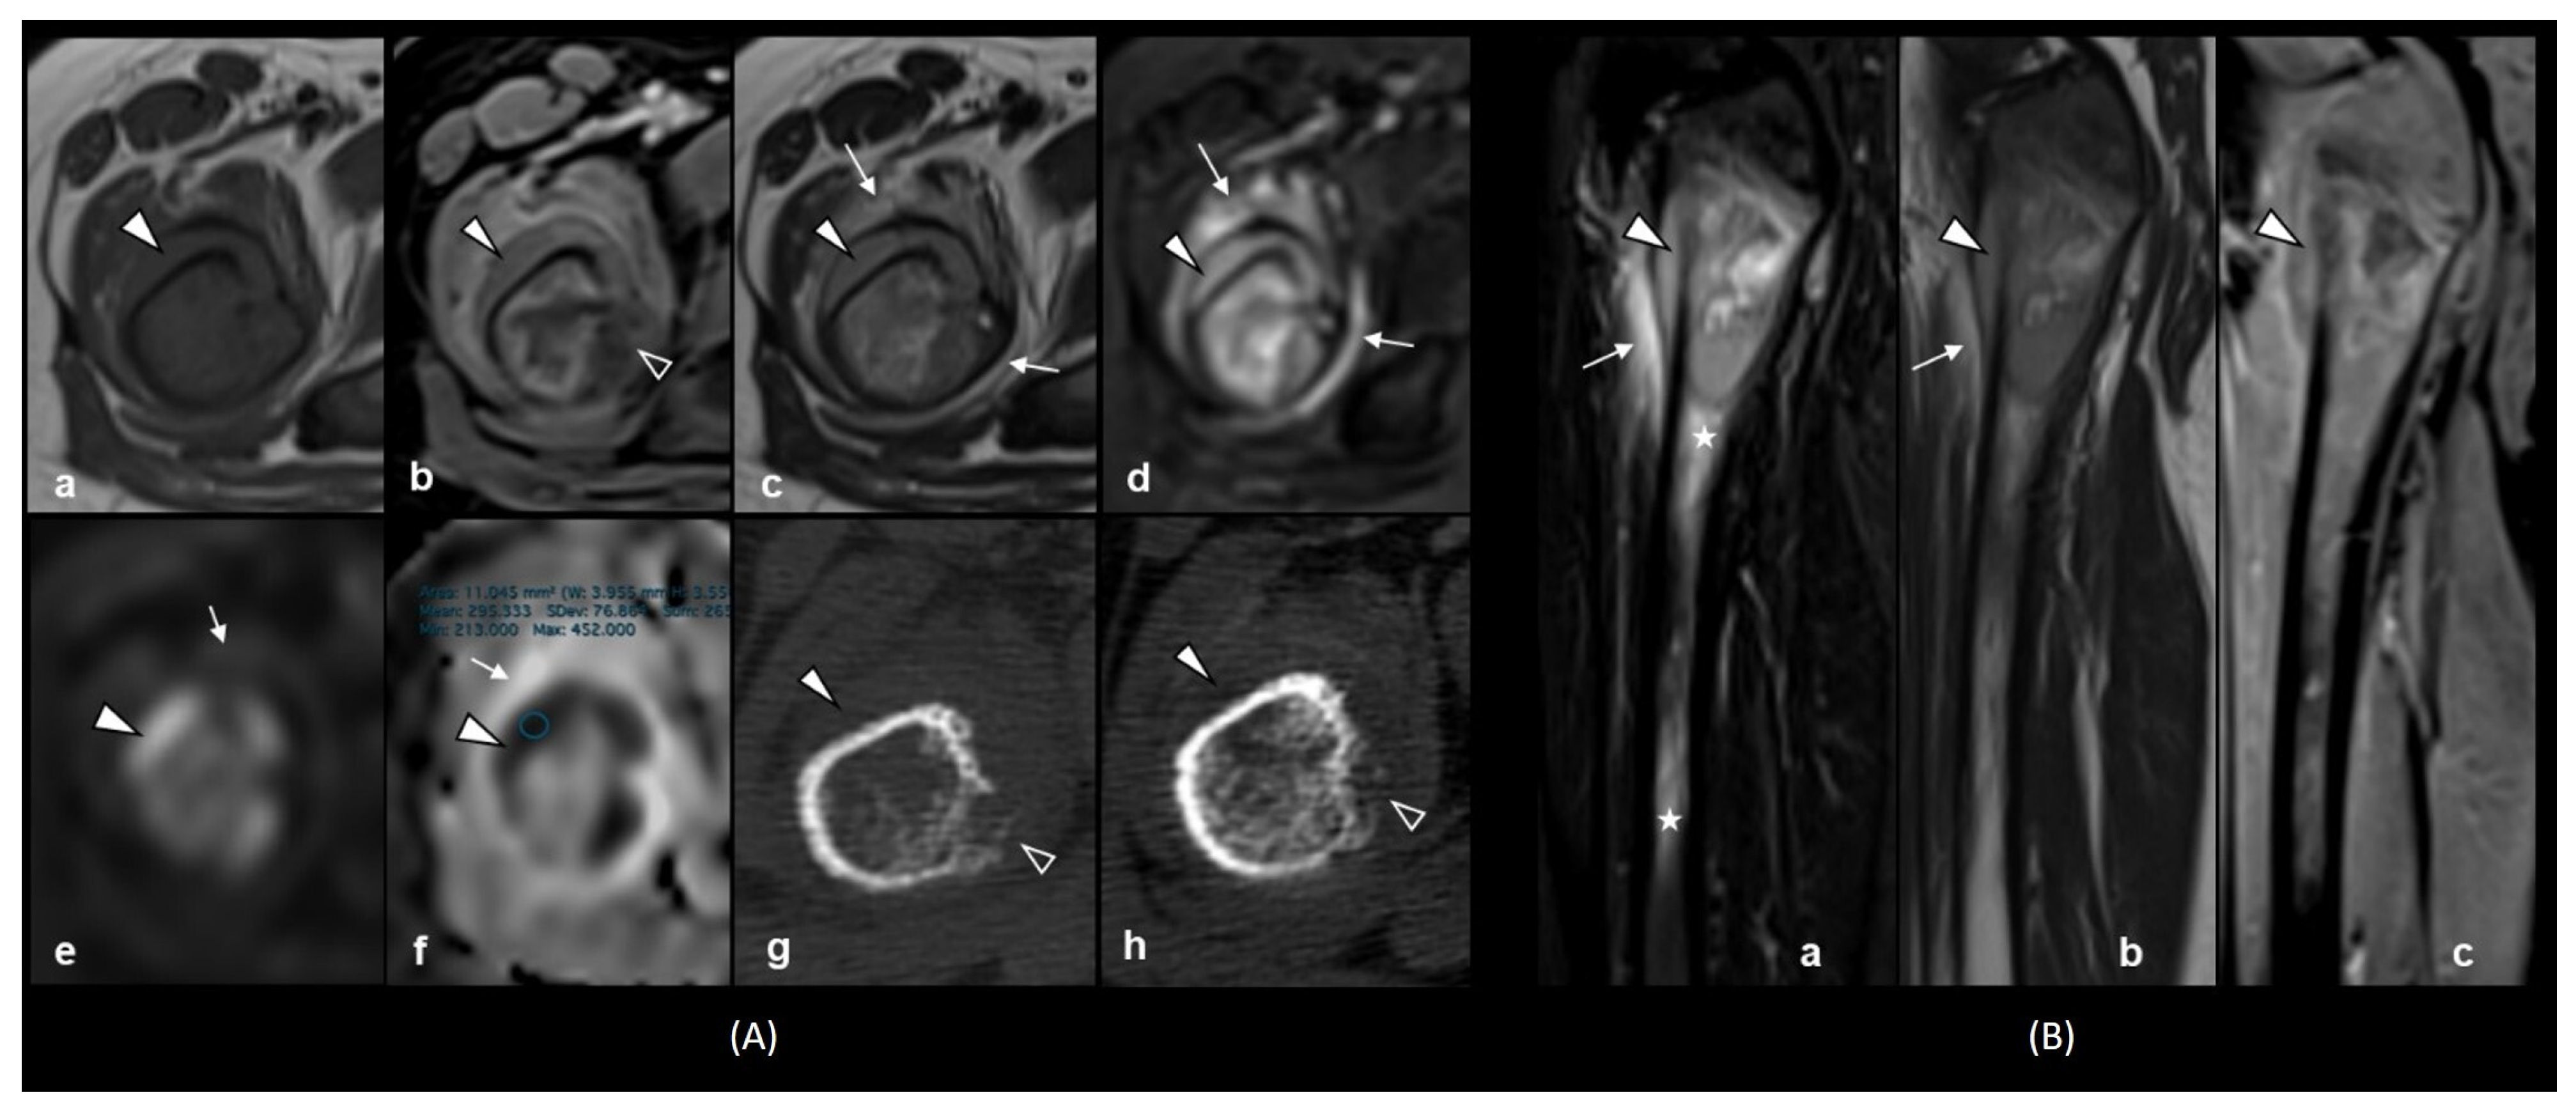

2. Case Presentation

- Meyer, H.J.; Beimler, M.; Borte, G.; Pönisch, W.; Surov, A. Radiological and Clinical Patterns of Myeloid Sarcoma. Radiology and Oncology 2019, 53, 213. [Google Scholar] [CrossRef]

- Surov, A.; Meyer, H.J.; Wienke, A. Correlation between apparent diffusion coefficient (ADC) and cellularity is different in several tumors: A meta-analysis. Oncotarget 2017, 8, 59492. [Google Scholar] [CrossRef] [PubMed]

- Wang, T.; Wu, X.; Cui, Y.; Chu, C.; Ren, G.; Li, W. Role of apparent diffusion coefficients with diffusion-weighted magnetic resonance imaging in differentiating between benign and malignant bone tumors. World J. Surg. Oncol. 2014, 12, 365. [Google Scholar] [CrossRef] [PubMed]

- Neubauer, H.; Evangelista, L.; Hassold, N.; Winkler, B.; Schlegel, P.G.; Köstler, H.; Hahn, D.; Beer, M. Diffusion-weighted MRI for detection and differentiation of musculoskeletal tumorous and tumor-like lesions in pediatric patients. World J. Pediatr. 2012, 8, 342–349. [Google Scholar] [CrossRef]

- Ibrahim, Y.A.; Elsadawy, M.E.; El Naggar, T. Role of quantitative diffusion-weighted imaging in differentiation between red and infiltrated marrow in pediatric patients with hematologic malignancy. Egypt. J. Radiol. Nucl. Med. 2019, 50, 1–5. [Google Scholar] [CrossRef]